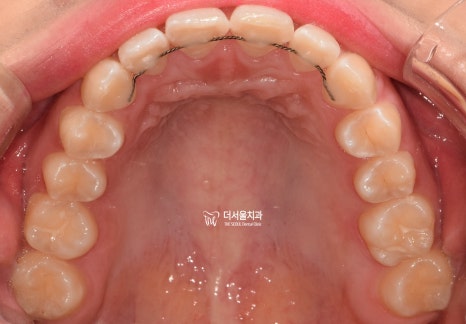

교합면에서 확인해 보았더니

U자에 가까워야 될 악궁의 형태가

사각형에 가까워져 있었습니다.